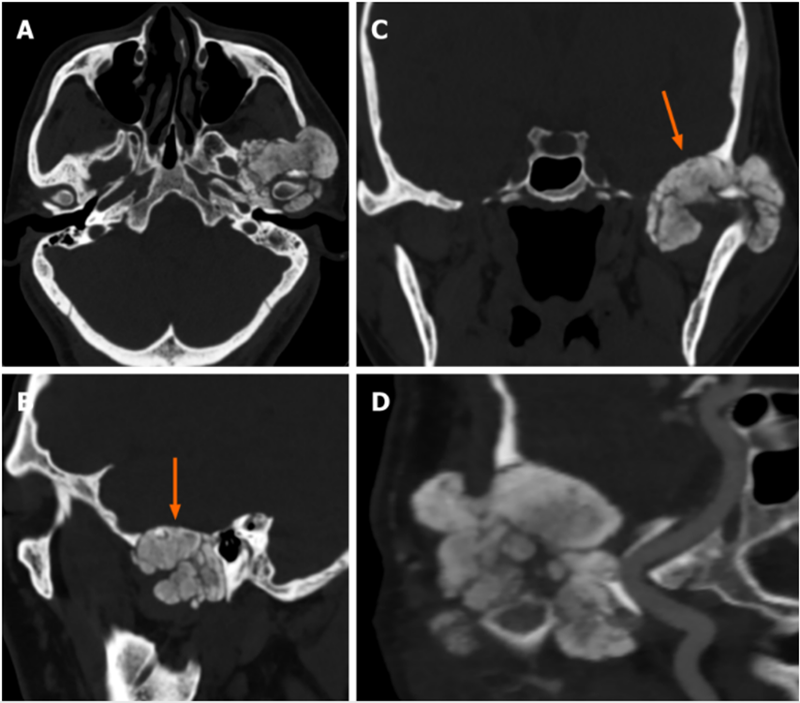

CPDD累及颞下颌关节

颞下颌关节侵犯了颅窝的钙焦磷酸沉积疾病